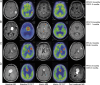

Patients and methods: This prospective study included 53 patients with PCNSL who underwent a high-dose methotrexate-based treatment. Brain FDG PET was performed at diagnosis (baseline PET) and after induction chemotherapy (interim PET), assessing interim PET parameters such as the highest maximum standardized uptake value (hSUV max ), sum of SUV max (sumSUV max ), highest tumor-to-normal ratio (hTNR max ), sum of TNR max (sumTNR max ), highest metabolic tumor volume (MTV) (hMTV), and sum of MTV (sumMTV) across all PET-positive lesions.

Results: High interim hTNR max (hazards ratio: 9.76, 95% confidence interval: 1.90-50.11, P = 0.01) was an independently significant predictor of poor progression-free survival in multivariate analysis. Patients with low interim hTNR max (≤1.0) had a significantly longer median progression-free survival than those with high interim hTNR max (>1.0) (25.0 vs 3.6 months, P < 0.001). Incorporating interim MRI-based clinical response assessments and hTNR max allowed the classification of partial response subgroups with markedly different prognoses ( P < 0.001). High interim hTNR max (hazards ratio: 2.76, 95% confidence interval: 1.39-5.48, P = 0.004) was an independently significant predictor of poor overall survival in multivariate analysis.